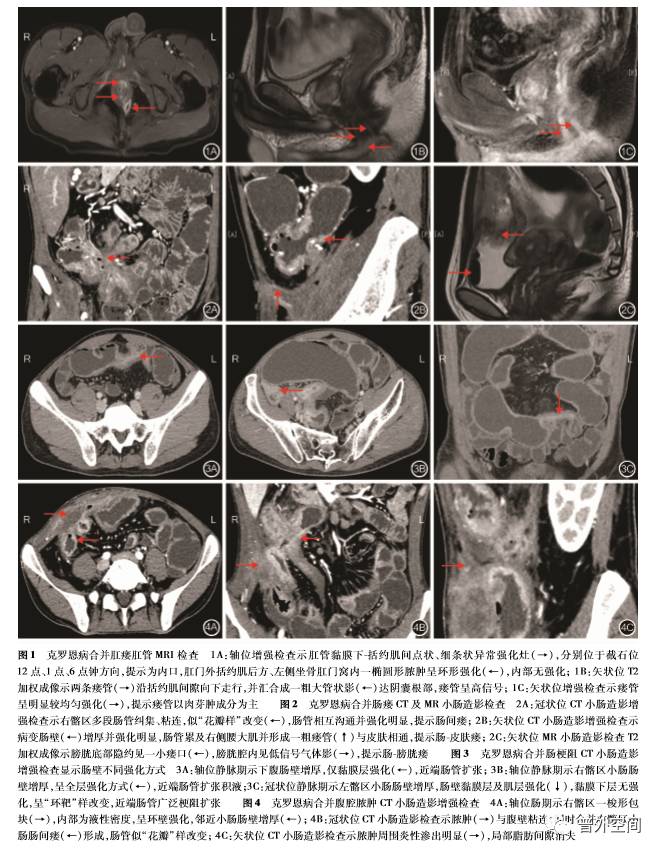

2. 3. 1 肛瘘或肛瘘合并肛周脓肿:71例肛瘘患者 中, 65例表现为 2个以上内口或瘘管的复杂性肛 瘘。内口为瘘管发出的起始点,肛管 MRI增强检查 示肛管黏膜下 括约肌间的点状、细条状或小圆形异 常强化灶。瘘管表现为水平或垂直走行的管状、索 条状结构,瘘管之间可交汇沟通。肛管MRI检查T2加权成像示瘘管呈稍高 高信号,增强检查示瘘管呈 明显较均匀强化或管壁强化、管腔无强化。3 8例肛 瘘合并肛周脓肿患者肛管MRI检查T2加权成像示 脓肿呈明显高信号,增强呈环形强化,内部无强 化[9]。见图1。

2. 3. 2 肠瘘: 2 6例肠瘘患者中, 1 7例出现肠间瘘。 CTE增强检查示多段肠壁增厚,较正常肠管强化明 显,肠管互相纠集、粘连,呈网状连接,形似花瓣样的 改变,呈“星征” [1 0]。1 4例患者出现肠 腹壁瘘(其 中6例合并肠间瘘、 1例合并肠间瘘及肠 膀胱瘘), 4例出现肠 膀胱瘘(其中2例合并肠间瘘、 1例合并 肠间瘘及肠 皮肤瘘),1例出现肠 阴道瘘,CTE或 MRE检查示病变肠管肠壁增厚,显示管道影与腹 壁、膀胱、阴道的直接相通,管状影T2加权成像呈高 信号,增强检查呈管壁强化;部分肠管与脏器空间位 置近,无管道直接沟通,仅显示邻近器官的异常强化 或局部积气。见图2。

2. 3. 3 肠梗阻:肠梗阻 CTE检查示增厚的肠壁管 腔变窄,合并近端肠管扩张。增厚肠壁强化方式不 一, 24例肠梗阻患者出现3种不同的强化方式:(1) 12例表现为肠壁黏膜层强化,黏膜下层及肌层无强 化;(2)4例表现为肠壁黏膜层及肌层强化,黏膜下 层无强化;(3)8例表现为肠壁全层均匀或不均匀强 化;其中前2种强化方式呈“环靶样”改变。见图3。

2. 3. 4 腹腔脓肿:2 3例患者并发腹腔脓肿,其中 15例同时合并肠瘘。CTE或MRE检查示腹部类圆 形或椭圆形的包块,T2加权成像呈高信号,周围系 膜出现炎性渗出,内部为液性密度,增强见边缘环壁 强化,内部脓液无强化。见图4。

针对克罗恩病合并的各种并发症,CTE、MRE 检查及肛管 MRI检查都具有鲜明的影像学特点。 肛瘘或肛周脓肿是克罗恩病常见的并发症,其具体 发生的机制尚不明确[2 1]。克罗恩病肛瘘往往比较 复杂,与常见的隐窝腺性感染形成的瘘管有着明显 的不同,其表现为多个内口、多条瘘管、多发脓肿的 高位复杂型肛瘘,有时难以用传统的 Pa r k′ s分型具 体地划分。本研究中有9 2%的患者发生复杂性肛 瘘。肛管MRI检查能多维度观察内口方位、主瘘管 及分支瘘管走行以及脓肿的大小位置。肛瘘影像学 表现为多条管道状走行的异常信号,瘘管呈明显较 均匀强化或管壁强化、管腔无强化,这与管腔内的成 分是肉芽肿或是脓液相关。肛瘘合并脓肿可发生在 肛周间隙,同样能发生在括约肌内,其部位不一、形 态多样,例如坐骨肛门窝脓肿表现为类圆形,耻骨直 肠肌脓肿表现为后马蹄形;由于内部脓液较多,T2 加权及弥散加权成像脓肿呈明显高信号,增强呈环 形强化,内部无强化。由于克罗恩病为肠壁全层透 壁性炎,炎症穿透肠壁深入系膜,产生窦道或肠管与 其他器官粘连形成通道时,就会出现肠瘘。肠瘘可 累及邻近的任何器官,形成肠 肠瘘、肠 膀胱瘘、肠 阴道瘘、肠 腹壁瘘等。肠内瘘相对外瘘更加常见, 其中肠间瘘最多见,表现肠管之间相互粘连、分界不 清,多段肠管花瓣样聚集,形成“星征”[1 0]。此外, 由于肠壁炎症长期、反复的刺激,可引起肠壁细胞外 基质成分发生改变,炎症细胞及纤维组织增多,从而 并发肠管狭窄,继发肠梗阻。肠梗阻表现为肠壁增 厚狭窄并异常强化,近端肠管扩张积液;增厚肠壁根 据病理成分的不同可分为纤维性或炎性狭窄,这在 T2加权图像信号、肠壁强化及其他功能成像上会有 不同的影像表现。腹腔脓肿在克罗恩病患者中也不 少见,其往往和肠瘘共同发生。脓肿可发生在腹部 的任何位置,包括系膜内、腹膜后、膈下、肠壁内、腹 壁内等。克罗恩病合并腹腔脓肿表现为系膜内、腹 壁、膈下或其他部位出现椭圆形或圆形的包块,周围 炎性渗出,脓肿壁出现强化。急性穿孔的直接征象 是肠壁出现缺损或瘘口,这在克罗恩病中很少出现, 本研究中影像学医师依据膈下或系膜旁出现游离气体的间接征象提示肠穿孔的诊断。克罗恩病除继发 肠道并发症外,亦可出现其他系统的肠外并发症,如 胆结石、门静脉血栓、硬化性胆管炎、肾结石、肾积 水、骨关节炎、虹膜炎、皮肤结节性红斑、坏疽性脓皮 病等[1 5]。本研究主要探讨肠道并发症,缺乏对肠外 并发症的研究,仅2例肠外表现患者亦合并有肠道 并发症。术后复发或二次并发症的患者,影像学表 现与术前基本类似。